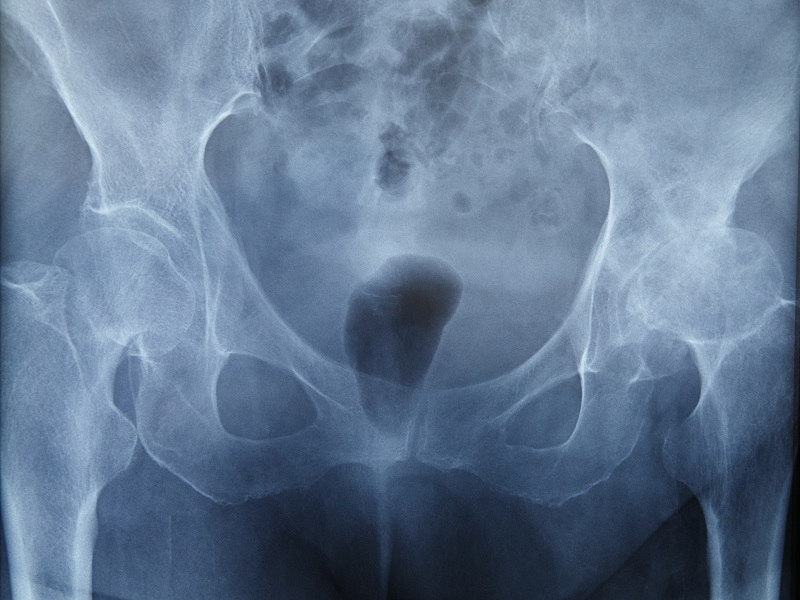

Оцінити стан і функціонування нирок і сечовивідних шляхів, виявити пухлини, камені, травми та інші захворювання або пошкодження органів сечостатевої системи допомагає урографія в Києві в клініці МЕДІКОМ. Урографія – це рентгенологічний метод дослідження органів сечовидільної системи.

- оглядова урографія – дозволяє оцінити стан і функціонування нирок, сечоводів, уретри й інших органів сечостатевої системи.

Оглядова урографія дозволяє виявити патологічне зморщування і розтягнення нирок, гіперплазію тканин органів сечостатевої системи, інфекційні ураження сечових шляхів, аномалії в положенні і рухливості нирок, наявність сторонніх тіл в сечовидільній системі.

Рентгенографія сечовидільної системи довела свою ефективність при виявленні патологій і травм. Вона дає досить повну морфологічну картину патологічних процесів, що відбуваються в паренхімі, мисках і чашечках нирки, в інших структурах органів сечовидільної системи. Наявність на урограмах різних контурів чашок і миски, які перебувають як у фазі систоли, так і у фазі діастоли, дозволяє уявити собі їх уродинаміку.